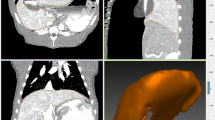

Three different measures of working space were analyzed: linear dimensions as measured on CT (Fig. 1) in a sagittal midline plane; maximum internal abdominal anteroposterior (AP) diameter from the front of the vertebral column to the anterior peritoneal lining; maximum distance between the upper border of the pubic symphysis and the highest diaphragmatic peritoneal lining; in a transverse and coronal plane; maximal internal diameter of the abdomen between the lateral peritoneal linings; and volume of the free intra-abdominal CO2 as measured on CT. Intra-abdominal volumes were calculated with the Syngo 3D volume module of a Siemens Navigator workstation using a data set of 5 mm slices. Free CO2 in the abdomen on transverse slices was detected semiautomatically after appropriate thresholds were defined. Slices could be integrated to a total volume of free intra-abdominal CO2. All volumes were visually checked for inadvertent inclusion of intraluminal gas in the bowel, which has the same CT density as CO2. Volume of insufflated CO2 as given by the insufflator (Endoflator, Storz).

Regarding the linear dimensions on CT (Fig. 2), the mean internal AP diameter increased by 3.2 cm (from 8.8 to 12 cm) when IAP was raised from 0 to 5 mmHg; a relative increase of 36 %. This diameter increased by another 2.2 cm (to 14.2 cm) when IAP was raised from 5 to 10 mmHg, a relative increase of 18 %. At the final step from 10 to 15 mmHg, the mean AP diameter increased by 0.8 cm, a relative increase of 5 %.

CT revealed a nonlinear increase of the abdominal volume with increasing pressure (Fig. 3). The pressure rise to 10 mmHg achieved the most gain in working space; the next step to 15 mmHg achieved much smaller gain.

Use of the volume of CO2 released by the insufflator as the only indicator of the amount of CO2 that is in the abdomen results in errors due to gas leakage, absorption of gas, and effects of temperature and compressibility. In contrast, multiplanar CT analysis of the working space is a reliable way to measure CO2 peritoneum and its linear dimensions because it clearly depicts the boundaries of the actual working space (Fig. 1) [37].